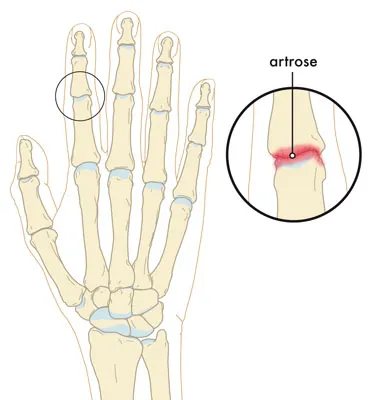

Vingerartrose is slijtage van de gewrichten in de vingers. Het betreft meestal de gewrichten van het middelste kootje (PIP-gewricht) en het eindkootje (DIP-gewricht). Door het verdwijnen van kraakbeen in deze kleine gewrichten ontstaat een versleten vingergewricht, met bot-op-bot contact. Het lichaam reageert met het vormen van extra bot rondom het gewricht, wat leidt tot zichtbare knobbels op de vinger. Deze knobbeltjes zijn kenmerkend. In de volksmond spreekt men soms van “slijtage vinger” of een “knobbel vinger”. Hoewel de misvormingen doen denken aan reuma, is vingerartrose een slijtageproces en geen ontstekingsziekte (zoals reumatoïde artritis). Met andere woorden: “reuma vinger” duidt meestal op een ander ziekteproces dan artrose.

- Röntgenonderzoek: op een röntgenfoto van de hand of vinger zijn de kenmerkende veranderingen bij vingerartrose zichtbaar. Men ziet versmalling van de gewrichtsspleet, botuitsteeksels (osteofyten) en soms kleine cystes in het bot onder het gewricht. Deze foto bevestigt de slijtage in het vingergewricht en helpt de ernst te beoordelen.

Vingerartrose aan de PIP- en DIP-gewrichten leidt tot pijnlijke en stijve vingers met vormveranderingen (knobbels). Het is een slijtageproces dat vaak in meerdere vingers optreedt naarmate men ouder wordt. Gelukkig zijn de klachten vaak mild en goed behandelbaar met eenvoudige maatregelen. In ergere gevallen van vingerartrose kunnen een vingerprothese of een arthrodese (vastzetten van de vinger) een goede uitkomst bieden om de pijn te verhelpen en de handfunctie te verbeteren.